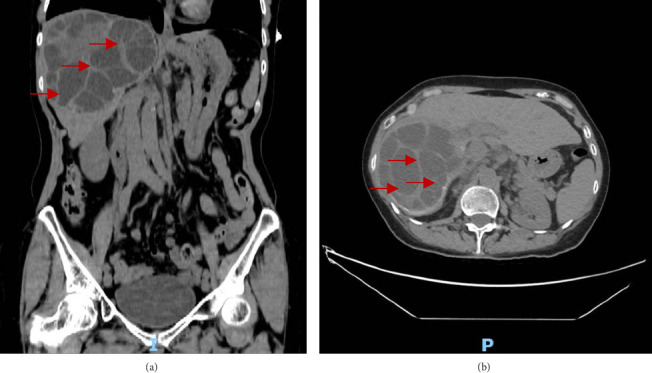

简介及重要性:囊性包虫病是流行地区常见的囊性感染。孤立性病变常见于肝脏,主要由细粒棘球绦虫引起。其他器官也可能受累,但程度较轻。本文报告一罕见的包虫性肝囊肿引起急性胰腺炎的表现。病例介绍:一名67岁女性,表现为右上腹疼痛、恶心和呕吐。她被发现有一个大的肝囊性包虫病占据肝脏右叶,并伴有急性胰腺炎。内窥镜逆行胆管造影(ERCP)后,发现三个小的黄色膜碎片(推测为子囊肿膜)阻塞了Vater壶腹处的胆总管。患者接受了腹腔镜下肝囊性包虫病开颅和腹腔镜胆囊切除术,术后过程平稳。临床讨论:肝囊性包虫病的治疗方式取决于囊肿的大小、影像学表现、囊肿活动状态和相关并发症。在非流行国家,由于来自流行地区的旅行而发生人口变化,因此需要高度的怀疑指数才能及时诊断。选择腹腔镜方法是因为其与微创手术相关的好处。虽然腹腔镜治疗肝囊性包虫病已有很好的报道,但其在急性胰腺炎合并病例中的应用仍然很少报道。结论:囊性包虫病最常见于肝脏。当合并急性胰腺炎时,通常需要阿苯达唑、ERCP和括约肌切开术联合入路,并根据囊肿分类进行手术切除。

Introduction and Importance: Cystic echinococcosis is a common cystic infection in endemic areas. Solitary lesions are commonly found in the liver and are primarily caused by Echinococcus granulosus. Other organs can be involved as well but to a lesser degree. This paper presents a rare manifestation of a hydatid liver cyst causing acute pancreatitis. Case Presentation: A 67-year-old female presented with right upper quadrant pain, nausea, and vomiting. She was found to have a large hepatic cystic echinococcosis occupying the right lobe of the liver with associated acute pancreatitis. After endoscopic retrograde cholangiopancreatography (ERCP), three small yellow membrane fragments-presumed to be daughter cyst membranes-were found obstructing the common bile duct at the ampulla of Vater. The patient underwent laparoscopic unroofing of the hepatic cystic echinococcosis and laparoscopic cholecystectomy with an uneventful postoperative course. Clinical Discussion: Treatment modalities for hepatic cystic echinococcosis depend on the size of the cyst, imaging findings, cyst activity status, and associated complications. In nonendemic countries, where demographic changes occur due to travel from endemic regions, a high index of suspicion is necessary for timely diagnosis. A laparoscopic approach was chosen for its benefits related to minimally invasive surgery. While laparoscopic management of hepatic cystic echinococcosis is well described, its use in cases complicated by acute pancreatitis remains infrequently reported. Conclusion: Cystic echinococcosis most commonly presents in the liver. When associated with acute pancreatitis, a combined approach involving albendazole, ERCP, and sphincterotomy is typically required, with surgical resection depending on cyst classification.